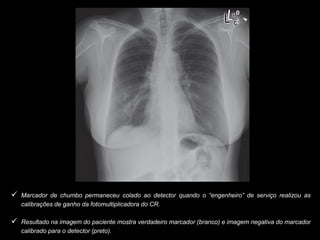

 Marcador de chumbo permaneceu colado ao detector quando o “engenheiro” de serviço realizou as

calibrações de ganho da fotomultiplicadora do CR.

 Resultado na imagem do paciente mostra verdadeiro marcador (branco) e imagem negativa do marcador

calibrado para o detector (preto).